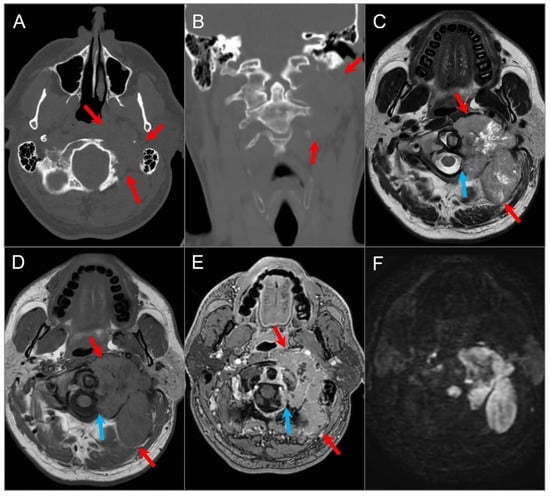

4.4.5. Paraganglioma